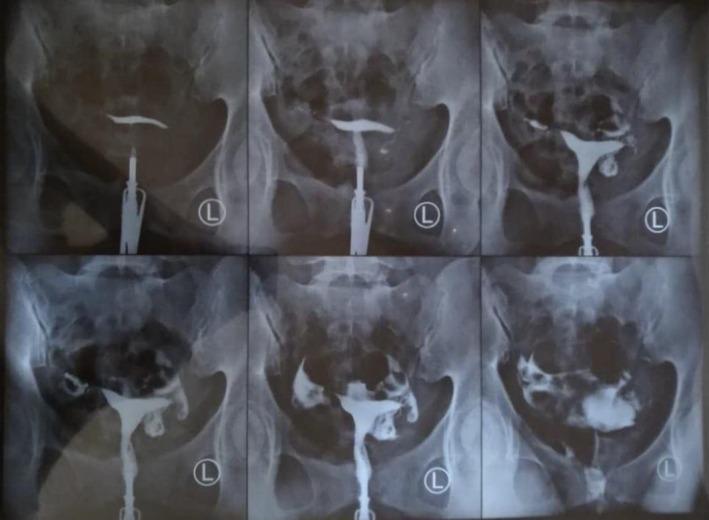

We present a novel approach combining hysteroscopic flushing and laparoscopic milking for tubal ectopic pregnancy (EP) removal while preserving fallopian tubes. Postoperative beta-human chorionic gonadotropin (β-hCG) suspected remnant EP, necessitating methotrexate. Three-month follow-up confirmed bilateral tubal patency. This technique offers a tube-preserving treatment for EP; however, β-hCG monitoring is crucial.

我们提出了一种新颖的方法,将宫腔镜冲洗和腹腔镜挤推相结合,用于在保留输卵管的同时移除输卵管异位妊娠(EP)。术后β-人绒毛膜促性腺激素(β-hCG)提示可能残留EP,因此需要使用甲氨蝶呤。三个月的随访证实双侧输卵管通畅。该技术为EP提供了一种保留输卵管的治疗方法;然而,β-hCG监测至关重要。